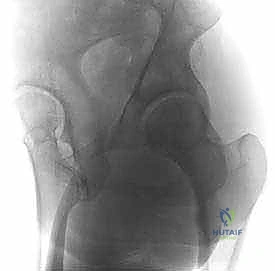

لفهم أهمية عملية قطع عظم الفخذ بين المدورين، يجب أولاً فهم تشريح مفصل الورك. يُصنف مفصل الورك كمفصل "كرة وتجويف" (Ball and Socket Joint). تتكون "الكرة" من رأس عظم الفخذ، بينما يتكون "التجويف" من التجويف الحقي (Acetabulum) في عظم الحوض.

تتصل الكرة ببقية عظم الفخذ عن طريق "عنق الفخذ". في الحالة الطبيعية للبالغين، يصنع عنق الفخذ زاوية مع جسم عظم الفخذ تتراوح عادة بين 125 إلى 135 درجة.

عندما تكون هذه الزاوية أكبر من الطبيعي (Coxa Valga) أو أصغر من الطبيعي (Coxa Vara)، يحدث خلل شديد في توزيع وزن الجسم على مفصل الورك. هذا الخلل يؤدي إلى تركيز الضغط على مساحة صغيرة جداً من الغضروف المفصلي، مما يسرع من تآكله ويؤدي إلى خشونة مبكرة (Osteoarthritis).

هنا يأتي دور الجراحة التقويمية التي يجريها الأستاذ الدكتور محمد هطيف؛ حيث يتم إجراء قطع عظمي دقيق في المنطقة الواقعة بين المدور الأكبر والمدور الأصغر (Intertrochanteric Region)، وهي منطقة تتميز بتروية دموية ممتازة مما يضمن التئاماً سريعاً للعظم. بعد القطع، يتم تعديل الزاوية لتوزيع الأحمال بشكل متساوٍ على مساحة أكبر من الغضروف السليم، مما يوقف أو يبطئ بشكل كبير عملية التآكل.